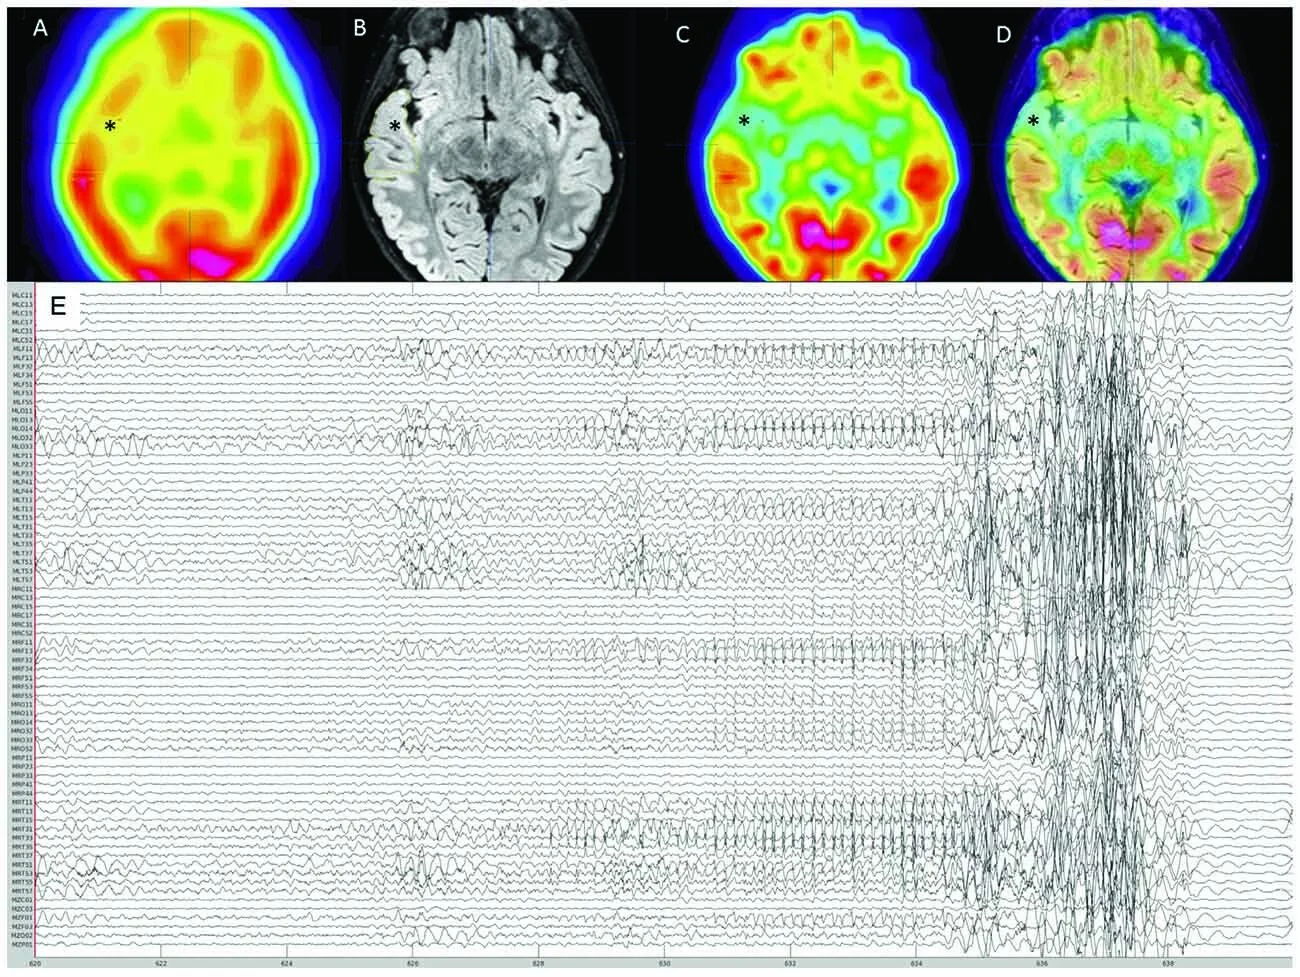

We performed a rare, 4h overnight MEG recording in an 8-yo w/ drug-resistant focal epilepsy & captured one ~45-s seizure. The patient underwent a selective right anterior temporal resection and remains seizure-free 21 months postoperatively.

The histopathological assessment confirmed frank focal cortical dysplasia (FCD) type IIa in the MEG-defined seizure onset zone (SOZ), which was based on source imaging of averaged ictal spikes at seizure onset.

We investigated temporal changes & spatial differences (SOZ vs. control areas) in spectral parameters of background brain activity (aperiodic broadband offset & slope) & assessed how they confounded the interpretation of variations of signal power in typical frequency bands of electrophysiology.

Our data show that the SOZ was associated with a higher aperiodic offset & exponent during the seizure compared to control regions. Both parameters increased in all regions from 2 min before the seizure onwards.

Regions anatomically closer to the SOZ also expressed higher values compared to contralateral regions, potentially indicating ictal spread. We also show that narrow-band power changes were caused by these fluctuations in the aperiodic component of ongoing brain activity.